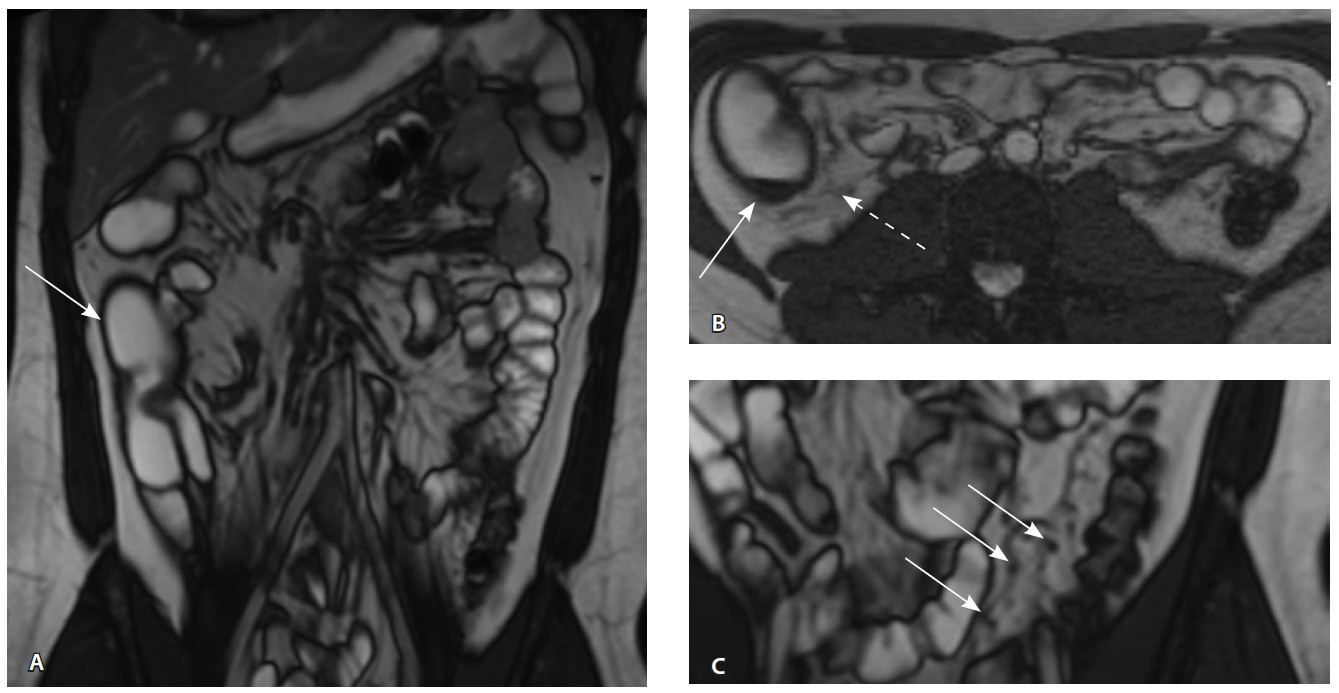

При мультиспиральной компьютерной томографии органов брюшной полости визуализировалась картина диффузного утолщения стенки толстой кишки с умеренным утолщением брыжейки и минимально выраженными явлениями лимфаденопатии в брыжейке (рис. 1).

Рис. 1. Мультиспиральная компьютерная томография органов брюшной полости с внутривенным введением контрастного вещества (йомепрол 350–100 мл), артериальная фаза: А – фронтальная проекция, Б – аксиальная проекция. Стрелками указано диффузное утолщение стенки толстой кишки и брыжейки